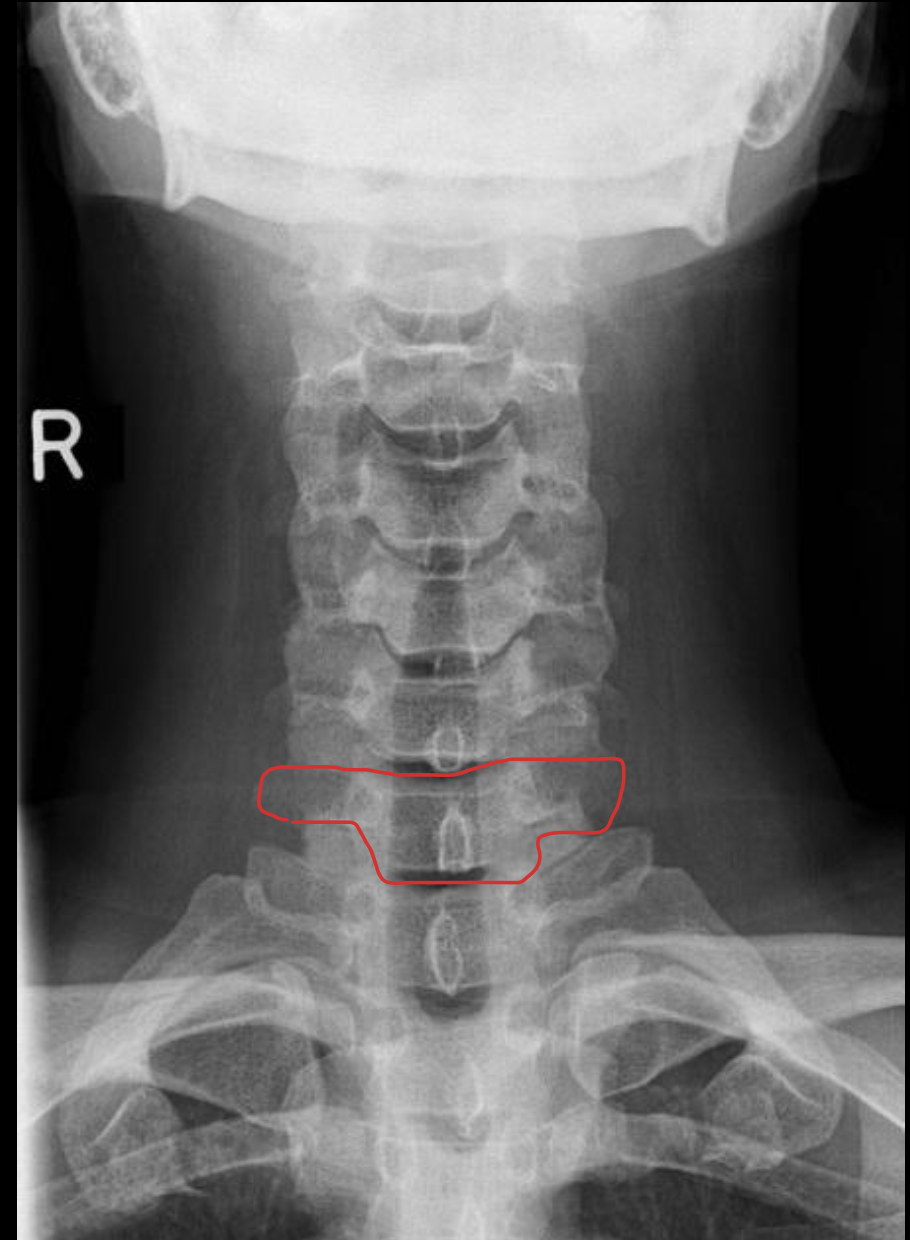

钩突

Uncinate process

关节柱 / 侧块

Articular pillars

棘突

Spinous process

椎间隙(Intervertebral Disc space)

IVD space

齿状突

Odontoid process C1

C7

T1

1st rib